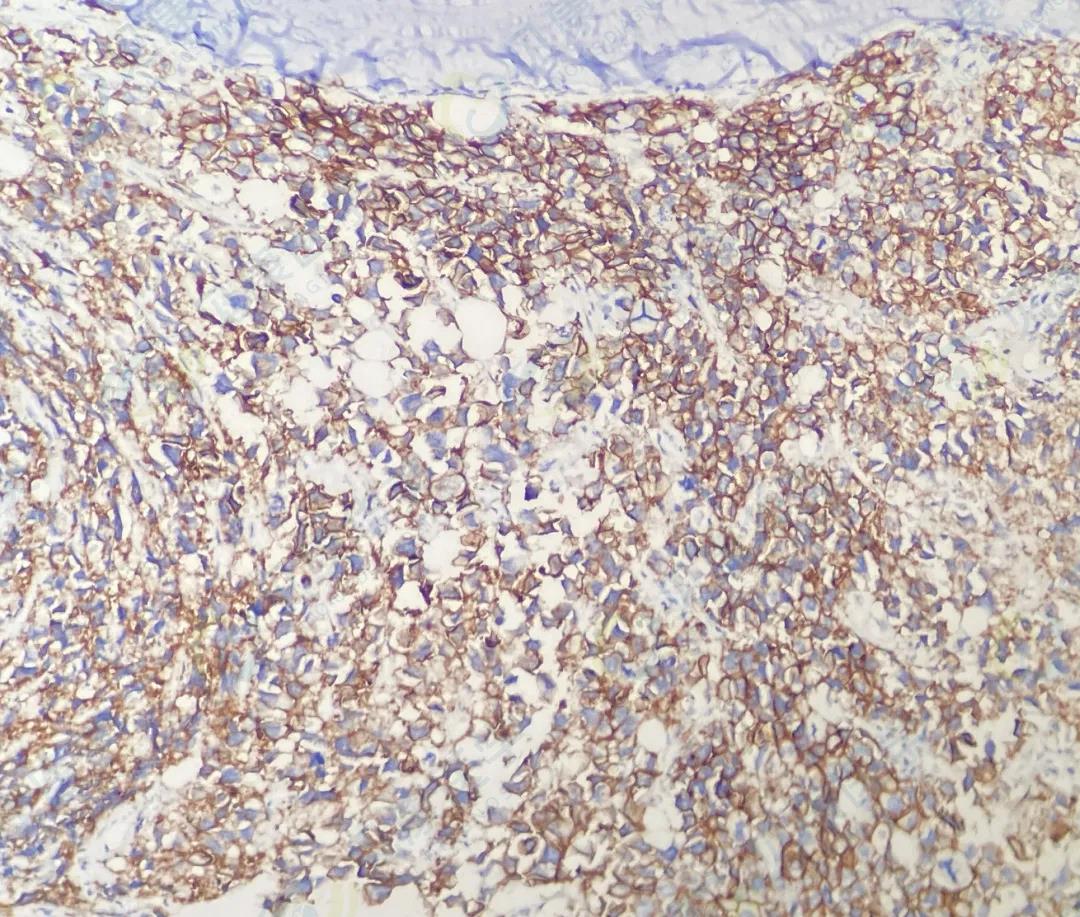

CD138

CD38

κ

λ